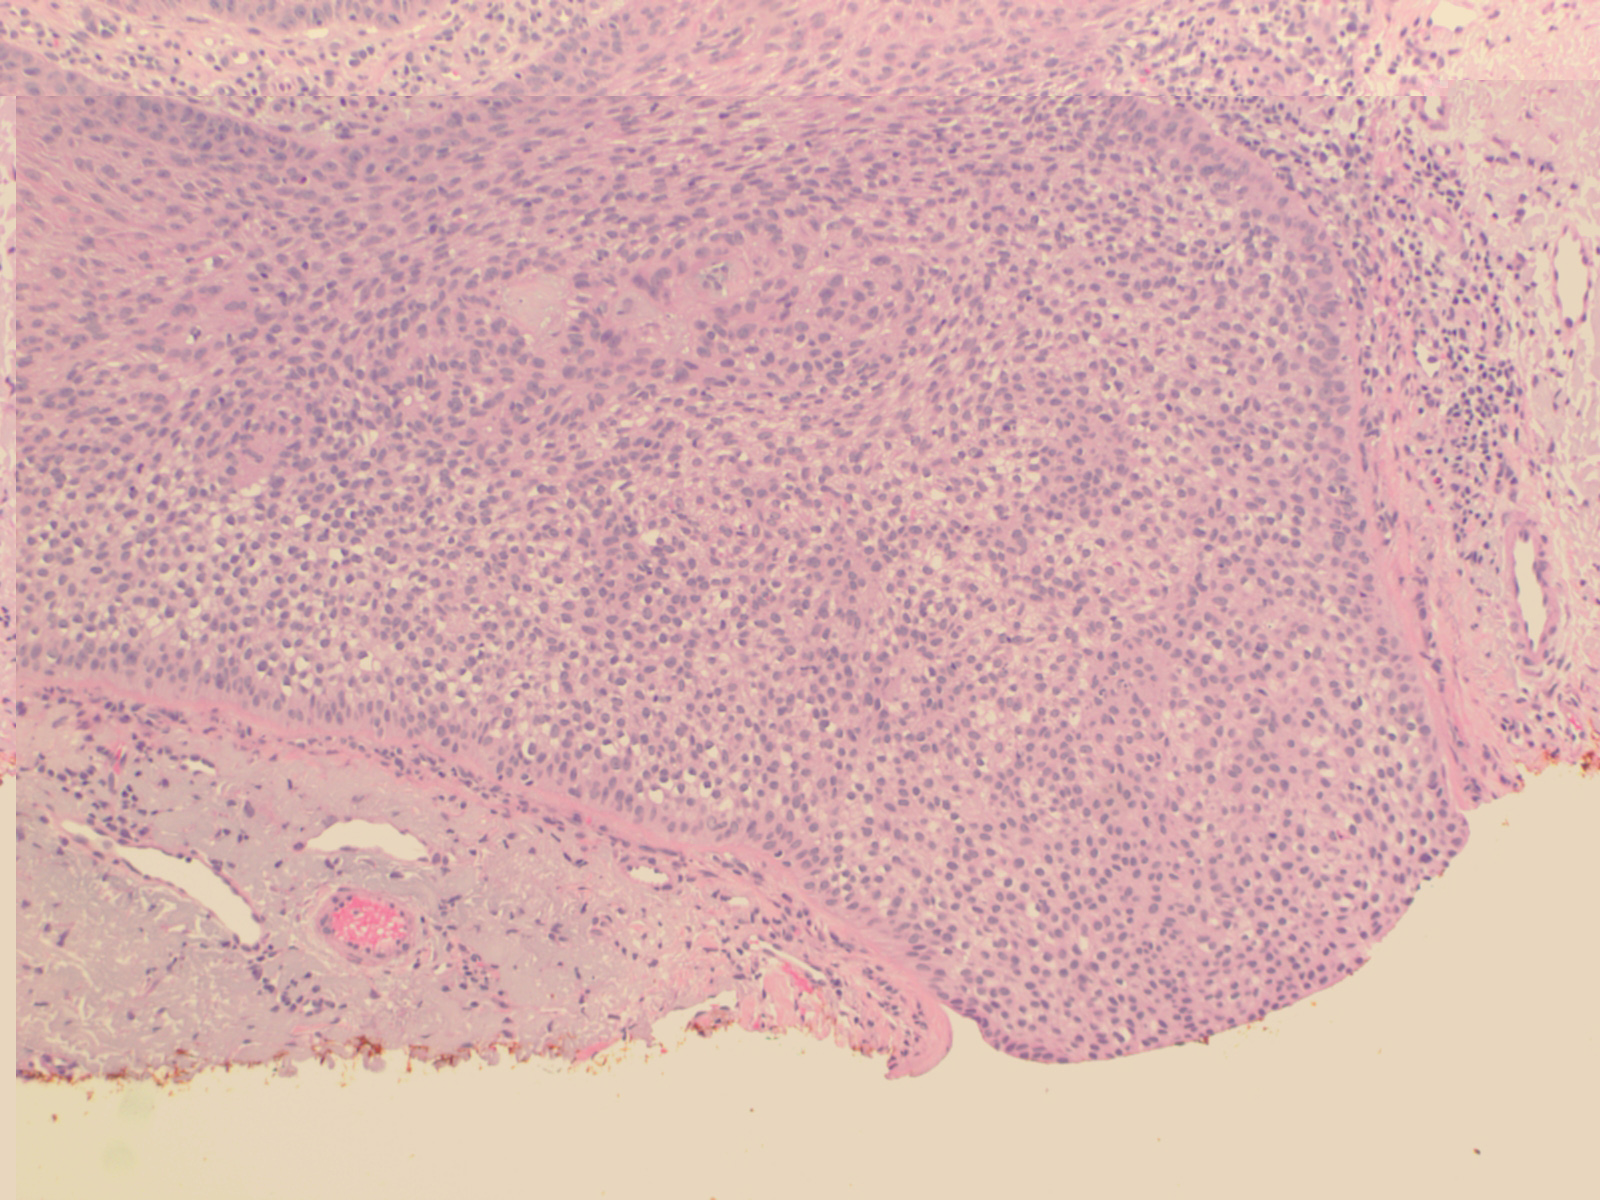

Trichilemmoma =ورم غمد جذر الشعرة